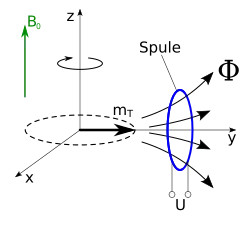

Einige Atomkerne (wie etwa die Wasserstoffkerne) in den Molekülen des zu untersuchenden Gewebes besitzen einen Eigendrehimpuls („Kernspin“) und sind dadurch magnetisch. Diese Kerne erzeugen nach dem Anlegen eines starken statischen Magnetfeldes eine kleine longitudinale Magnetisierung in Richtung des statischen Feldes (nuklearer Paramagnetismus). Durch ein kurzzeitig angelegtes zusätzliches hochfrequentes Wechselfeld mit der passenden Resonanzfrequenz im Radiofrequenzbereich lässt sich diese Magnetisierung aus der Richtung des statischen Feldes auslenken (kippen), also teilweise oder ganz in eine transversale Magnetisierung umwandeln. Die transversale Magnetisierung beginnt sofort zu präzedieren, d. h. um die Feldrichtung des statischen Magnetfeldes zu rotieren.

Diese sogenannte Larmorpräzession ist mechanisch analog an einem Spielzeugkreisel zu beobachten, wenn seine Drehachse nicht senkrecht steht, sondern um die Senkrechte herum eine Präzession vollführt (siehe Abbildung mit präzedierendem Gyroskop).

Die Präzessionsbewegung der Gewebemagnetisierung induziert – wie die Rotation des Magneten im Dynamo – eine elektrische Spannung in einer resonant abgestimmten Empfangsspule und kann damit nachgewiesen werden. Nach Abschalten des hochfrequenten Wechselfeldes nimmt die transversale Magnetisierung (wieder) ab, und die Spins richten sich wieder parallel zum statischen Magnetfeld aus. Für diese sogenannte Relaxation benötigen sie eine charakteristische Abklingzeit. Diese ist von der chemischen Verbindung und der molekularen Umgebung abhängig, in der sich der präzedierende Wasserstoffkern befindet. Daher unterscheiden sich die verschiedenen Gewebearten charakteristisch in ihrem Signal, was zu verschiedenen Signalstärken (Helligkeiten) im resultierenden Bild führt. Um den Ort der jeweiligen Atomkerne für die Bildgebung zu bestimmen, werden zusätzliche inhomogene ortsabhängige Magnetfelder (Magnetfeldgradienten) angelegt.

Wird ein solcher Kern in ein statisches magnetisches Feld gebracht, so ist seine Energie am niedrigsten, wenn das magnetische Dipolmoment zum Feld parallel ausgerichtet ist. Auf alle anderen Atomkerne wirkt ein Drehmoment, das die Richtung des magnetischen Moments in die Richtung des Magnetfeldes zu drehen versucht. Wegen des Eigendrehimpulses des Atomkerns und der Drehimpulserhaltung resultiert daraus die Präzessionsbewegung, d. h. die Drehimpulsorientierung des Kerns dreht sich ohne Änderung des Anstellwinkels um die Richtung des angelegten Magnetfeldes.

In einer Messspule wird durch die rotierende Transversalmagnetisierung eine Wechselspannung induziert. Ihre Frequenz ist die Larmorfrequenz, die bei einem statischen Gradientenfeld vom Ort abhängt, ihre Amplitude gibt die Stärke der Transversalmagnetisierung an, die ihrerseits von der genauen Folge (Sequenz) von Pulsen, vom Ort und vom Gewebetyp abhängig ist.